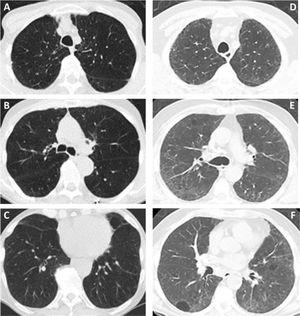

(A–F) Diffuse lung disease at baseline LDCT. Advanced destructive pulmonary emphysema (A–C) in a 65-year-old man from NLST who died of respiratory disease (ICD code J449) 835 days after randomization. Interstitial lung disease (D–F) in a 73-year-old man from NLST who died of respiratory disease (ICD code J849 – interstitial pulmonary disease unspecified) 2462 days after randomization.